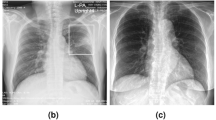

From March to October 2020, Quzhou City conducted a large-scale campaign involving active screening of all residents aged 65 years or older in the rural areas. The active tuberculosis screening intervention among the elderly was led by health administrative departments at the county level, organized and launched by township people’s governments, and supervised by county-level medical institutions. This mass screening involved a comprehensive physical examination and chest X-rays on all enrollees26. The majority of chest X-ray radiographic examinations for tuberculosis were scheduled at township health centers, as most of these centers have radiographic equipment. Among the 89 township health centers, seven that lacked on-site chest digital radiography (DR) equipment utilized mobile chest DR units for screening. Screening for tuberculosis was scheduled to coincide with the residents’ annual physical examination. At township health centers, targeted individuals underwent general health examinations and chest X-ray screenings27; images were uploaded to the local county hospital through the Picture Archiving and Communication System (PACS) for radiological interpretation, with the results subsequently fed back to the township health centers. A diagnostic panel composed of three members (two infectious disease specialists and one radiologist) was responsible for identifying abnormalities in participants’ chest radiographs and classifying the radiographic diagnoses into normal or abnormal28. Abnormal signs were further categorized into active lesions, stable lesions, and indeterminate lesions. Stable signs were subclassified into fibrotic lesions, sclerotic lesions, and calcified lesions29,30,31, while uncertain signs were subclassified into patchy and non-patchy lesions30,31. For abnormal classification, diagnostic results consensus from at least two specialists; disagreements were resolved through discussion until consensus was reached. The diagnostic panel included qualified licensed physicians, with at least one being a certified attending hospital physician (or more senior in terms of experience). All panelists received training from the Quzhou City Quality Control Center for Tuberculosis Diagnosis and Treatment. During on-site quality control, experts randomly reviewed a certain percentage of X-ray images; a concordance rate of over 90% between the evaluated image decisions and the quality control team was deemed acceptable. For individuals with active lesions, referral to designated tuberculosis hospitals for TB diagnostic tests was made to confirm or rule out active pulmonary tuberculosis. Those without active lesions were advised to seek tuberculosis diagnosis at designated hospitals if tuberculosis-related symptoms developed. In asymptomatic individuals with a chest X-ray result indicating an abnormality, referral to an appropriate healthcare facility for further evaluation and management was recommended to evaluate for other serious conditions such as lung cancer or pulmonary fibrosis. Pulmonary tuberculosis diagnosis primarily relied on pathogen detection (including bacteriological and molecular biological methods), combined with epidemiological history, clinical presentation, chest imaging, relevant ancillary tests, and differential diagnosis for comprehensive analysis. Bacteriological examinations included three sputum samples for Mycobacterium tuberculosis smear microscopy (one immediate, one morning, and one night sample), liquid culture of one sputum sample, and one GeneXpert MTB/RIF test24. When sputum volume or quality was inadequate, artificial sputum induction was performed, and bronchoalveolar lavage was used when necessary to obtain sputum samples.

Active signs: including multiple nodular lesions, patchy, cloudy flocculent and lobar lung consolidations, mass-like opacities, and enlarged hilar or mediastinal lymph nodes. These lesions are featured by heterogeneous density, high central density, peripheral low density, irregular distribution, and infiltrative changes. They may be accompanied by thick-walled, thin-walled, tension cavities, and multiple moth-eaten cavities, as well as satellite lesions, bronchial dissemination, bronchial dilation, lymphangitis, and pleural effusion. Stable signs: including dense nodules, plaques, calcified nodules, fibrous strands and residual purification cavities after treatment. These lesions have clear and sharp margins and may accompany pleural and/or mediastinal lymph node calcifications. Dense nodules and plaques are classified as sclerosing lesions, fibrous striated lesions are classified as fibrotic lesions. Calcified nodules and residual purgative cavities after treatment are classified as calcified lesions. Uncertain signs: including patchy lesions and non-patchy lesions (destroyed lungs, atelectasis, tuberculomas) and other lesions that have not yet been fully calcified, cannot make a diagnosis of inactive pulmonary tuberculosis based on these signs alone; further analysis after obtaining computed tomography scans is required28.